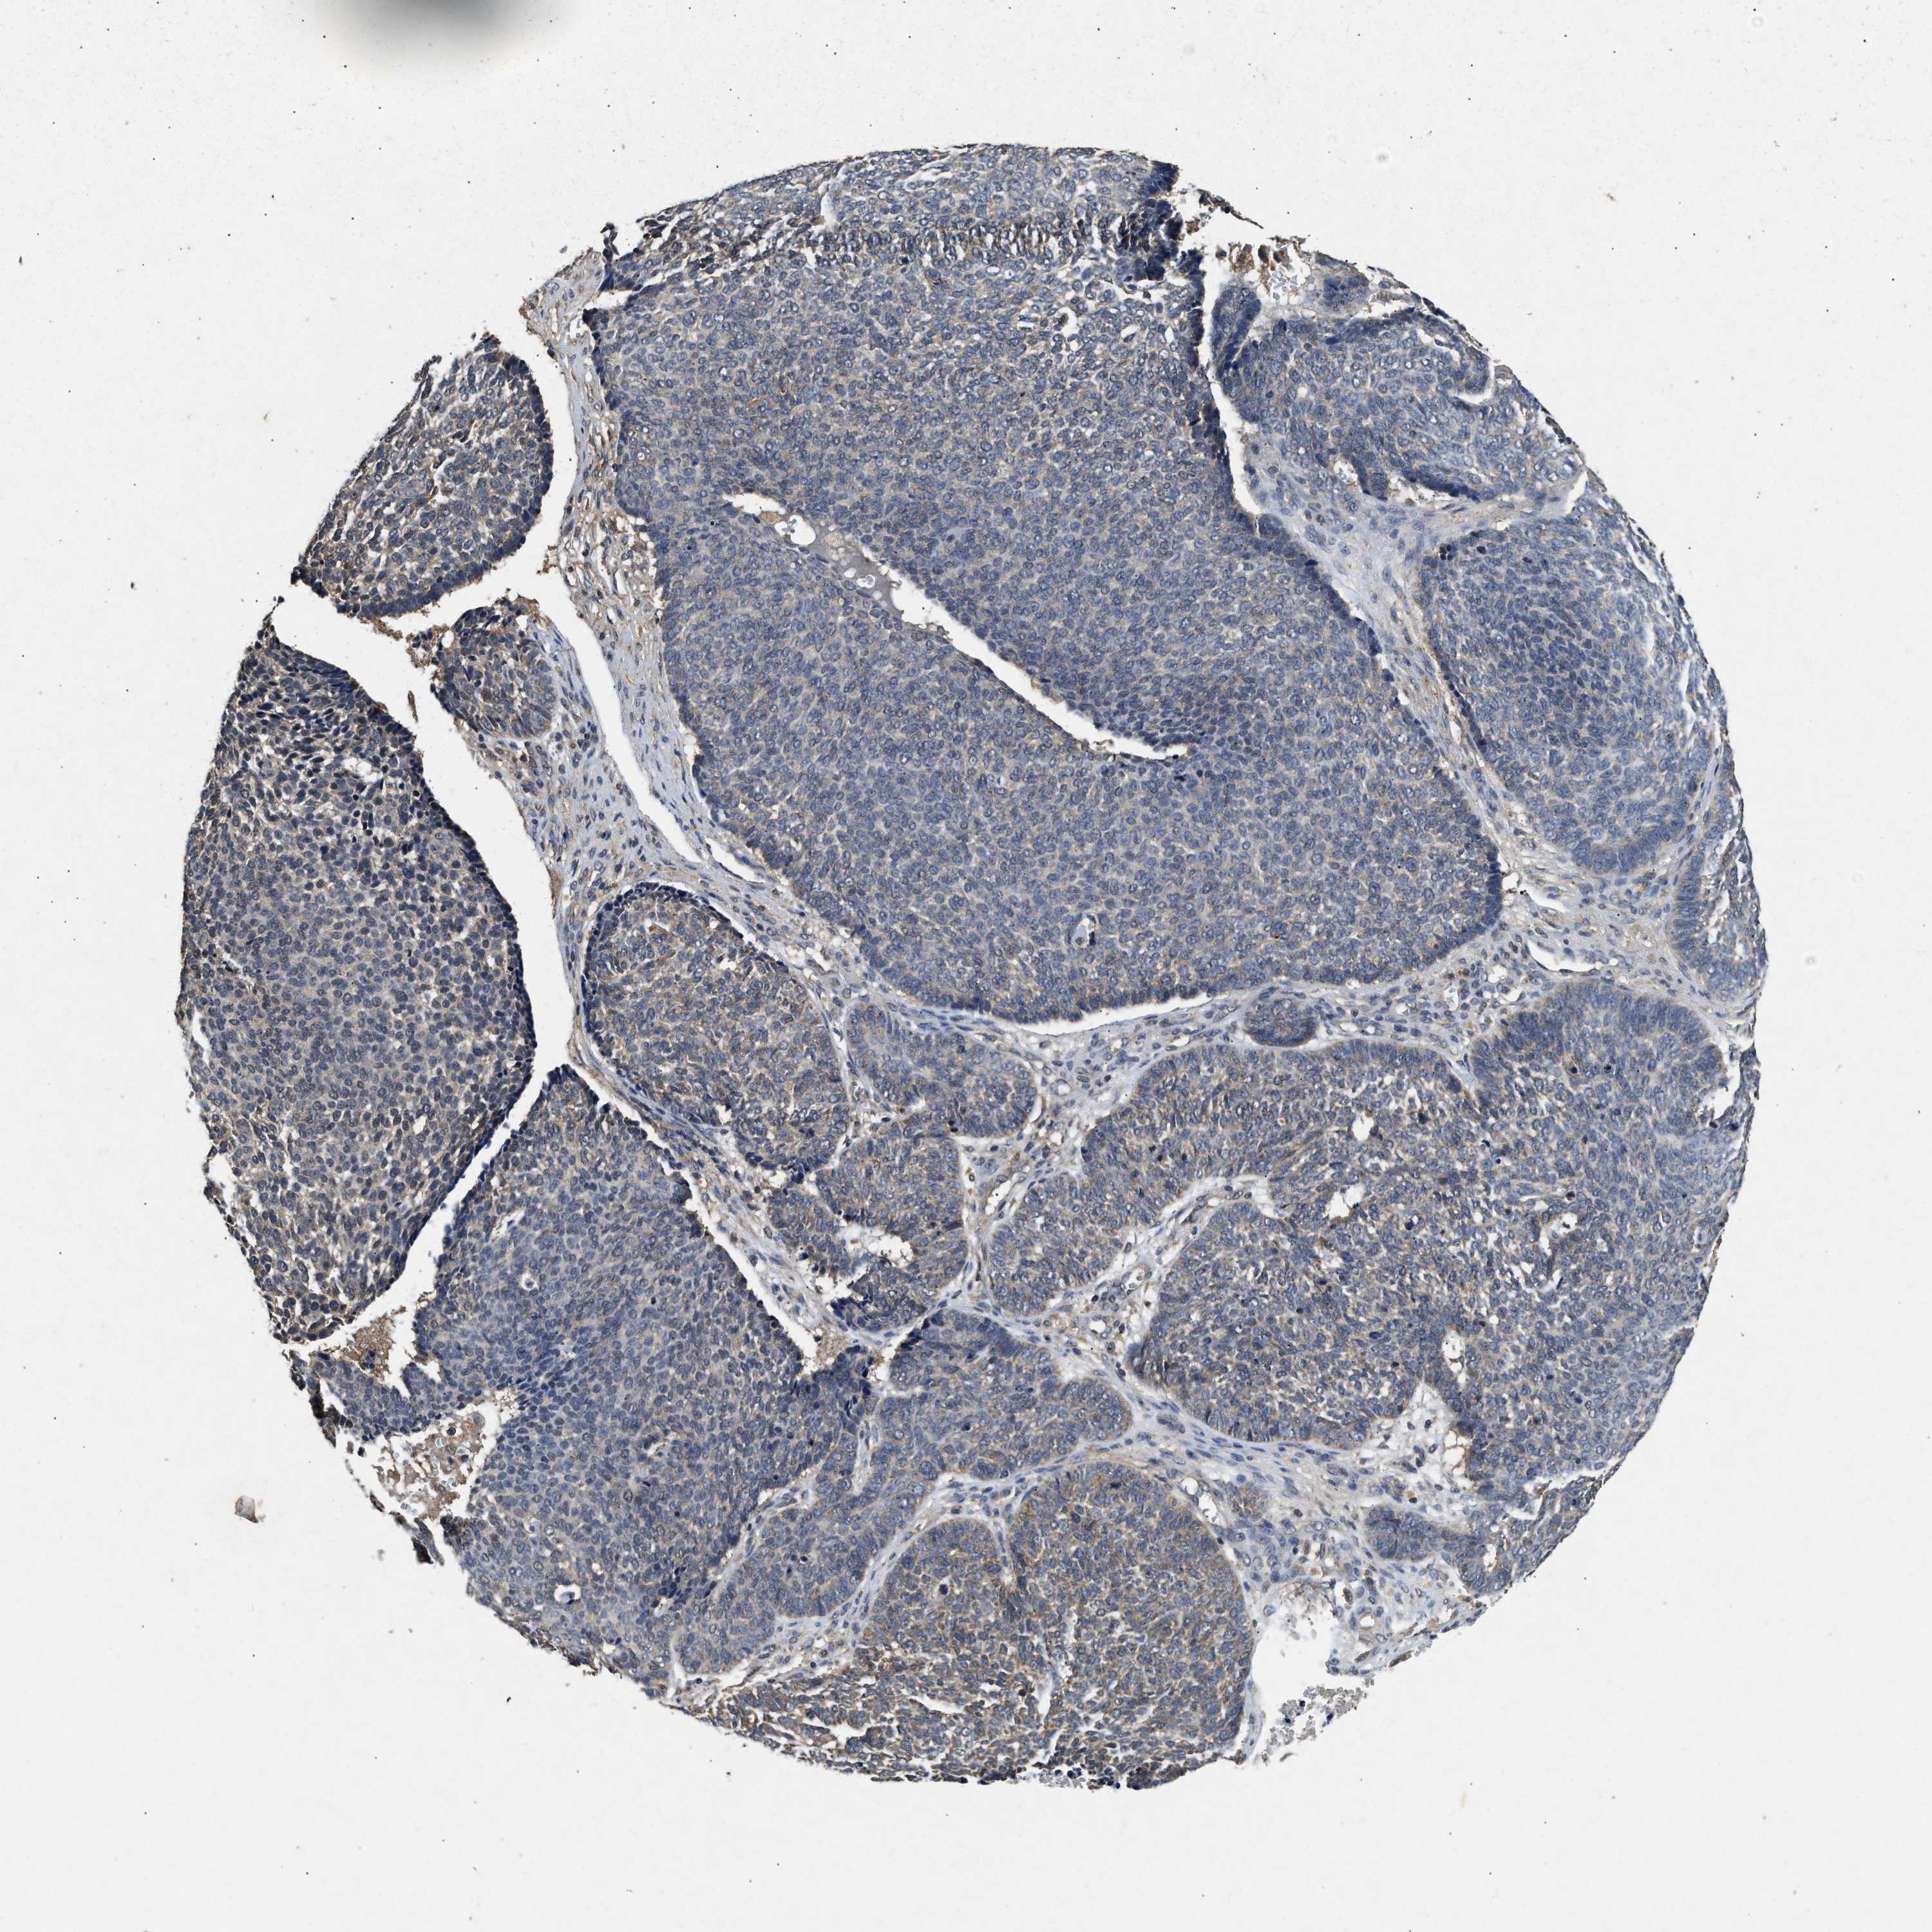

Basal cell and squamous cell cancer

SKIN CANCER - Protein expressioni

A mouse-over function shows sample information and annotation data. Click on an image to view it in a full screen mode. Samples can be filtered based on level of antibody staining by selecting one or several of the following categories: high, medium, low and not detected. The assay and annotation is described here.

Each image is clickable and will lead to virtual microscopy that enables deeper exploration of all samples and also displays staining intensity scores, fraction scores and subcellular localization as well as patient and tissue information for each sample.

Antibody HPA050294

Antibody HPA060836

Antibody CAB021103

Basal cell carcinoma

Squamous cell carcinoma, NOS